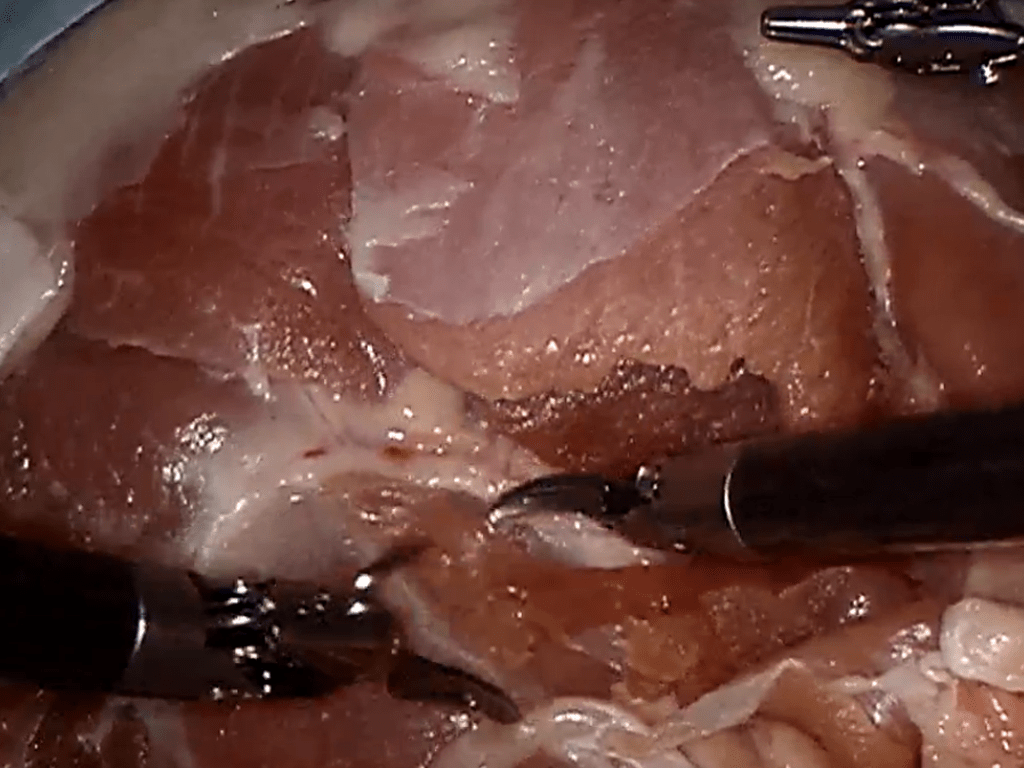

Reduction in Surgical Site Infections (SSI)

Clinical Initiatives to reduce Surgical Site Infections – Children’s Hospital desire to improve outcomes and reduce medical errors

Interventions aimed at reducing SSI rates were developed from published best practices and the institution’s internal observations and thoughts

- Developed process and procedures built around evidence based best practices, teamwork, and communications